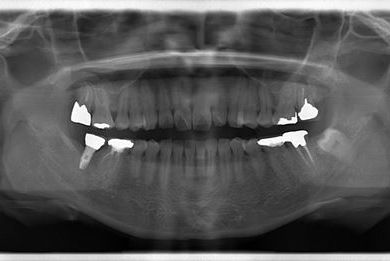

インプラント治療+セラミック治療+歯肉歯槽骨整形

| 性別/年齢 | 女性 / 38歳 | ||||||||||||||||||||||||||||||||

| 主訴 | 右下奥の欠損のため、インプラントを希望。また、左に物が挟まりやすいための治療も希望。 | ||||||||||||||||||||||||||||||||

| 治療方針 | 欠損部分を、インプラント治療にて、機能的・審美的回復を行う。 | ||||||||||||||||||||||||||||||||

| 治療内容 | インプラント1本、ジルコニアフレームオールセラミッククラウン2本(ジルコニアセラミック用土台1本)、歯肉歯槽骨整形 | ||||||||||||||||||||||||||||||||

| 総治療費 | 713,580円 | ||||||||||||||||||||||||||||||||

| 治療期間 | 10ヶ月 |